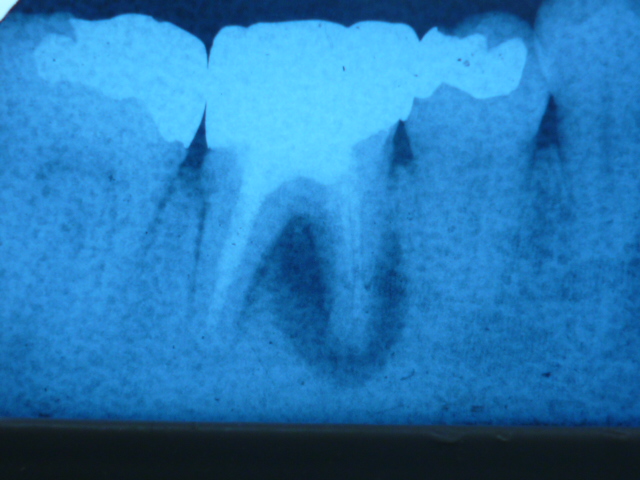

できるだけ歯を残すために—当院の症例紹介

当院では、可能な限り歯を残す治療を行っています。

こちらの患者さんは、他医院で「抜歯が必要」と説明を受け、当院へ来院されました。

診断の結果、私も抜歯の可能性が高いと判断しましたが、患者さんと相談し、

抜歯の可能性を理解いただいた上で、保存を目指した治療を開始しました。

症例写真1:術前

症例写真2:術後6ヶ月

この患者さんは、最終的に歯を残すことができました。状態によっては自費治療の高度な技術が必要となるケースもあります。